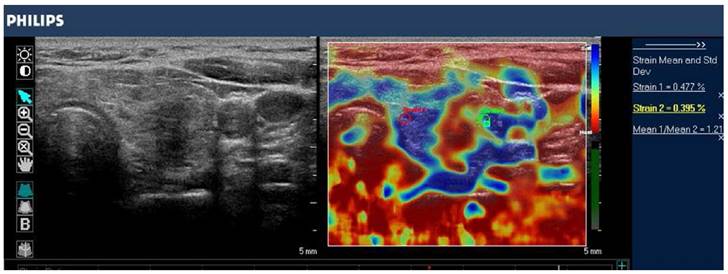

Figure 8

B-mode image (left) and color-coded elastogram (right) of a thyroid nodule in the left thyroid gland, imaged with SE on a Philips iU22 system. The nodule appears hypoechoic with ill-defined borders on anatomical B-mode image. The elastogram shows normal thyroid tissue encoded with blue color (soft tissue) and the nodule with red color (stiff tissue), suggesting a malignant nodule. This was confirmed by histology which showed papillary thyroid carcinoma.

Theranostics Image